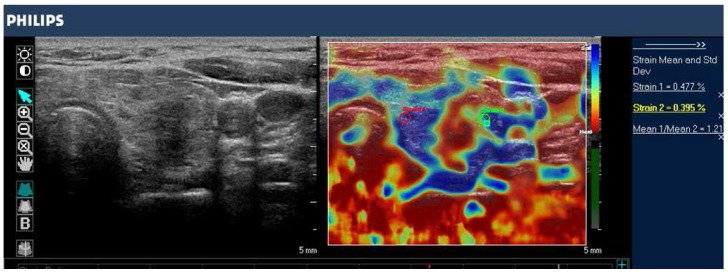

تصویربرداری از فشار سونوگرافی تیروئید

مطالعات تصویربرداری فشار اولتراسوند تیروئید را می توان بر اساس انواع محرک ها و سیستم های امتیازدهی طبقه بندی کرد. رایج ترین محرک مورد استفاده در تصویربرداری کرنش اولتراسوند تیروئید، فشرده سازی خارجی اعمال شده توسط اپراتور از طریق مبدل اولتراسوند است (شکل 8.8). روش دیگر، محرک فیزیولوژیکی با استفاده از ضربانهای شریان کاروتید برای القای حرکت غده تیروئید مجاور با نتایج دلگرمکننده مورد مطالعه قرار گرفته است. الاستوگرافی سونوگرافی پستان، 84 یا معیار راگو، امتیاز 5 امتیازی 86) و شاخص سفتی تیروئید نیمه کمی (کرنش در پس زمینه تیروئید نرمال / فشار در ندول تیروئید) . معیار آستریا بر اساس چهار دسته از سفتی بافت: امتیاز 1 برای گره های نرم. امتیاز 2 و 3 برای گره هایی با درجه سفتی متوسط. نمره 4 برای ضایعات سفت . به طور مشابه، معیار راگو از نمره 1 (یکنواخت کشسانی در کل ندول) تا نمره 5 (بدون کشش در ندول یا در ناحیه ای که سایه های خلفی را نشان می دهد) متغیر است.

تصویر حالت B (سمت چپ) و الاستوگرام با کد رنگی (راست) از یک گره تیروئید در غده تیروئید چپ، با SE در سیستم فیلیپس iU22 تصویر شده است. ندول هیپواکویک با مرزهای نامشخص در تصویر آناتومیک حالت B به نظر می رسد. الاستوگرام بافت نرمال تیروئید را با رنگ آبی (بافت نرم) و ندول را با رنگ قرمز (بافت سفت) نشان می دهد که نشان دهنده ندول بدخیم است. این مورد توسط بافت شناسی که کارسینوم پاپیلاری تیروئید را نشان می داد تایید شد.